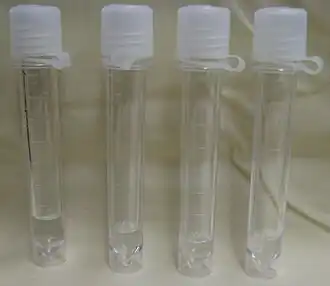

Viales con líquido cefalorraquídeo. | ||

El líquido cefalorraquídeo (LCR) o líquido cerebroespinal (LCE) es un líquido incoloro que baña el encéfalo y la médula espinal. Circula por el espacio subaracnoideo, los ventrículos cerebrales y el conducto ependimario sumando un volumen de entre 100 y 150 ml, en condiciones normales.[1]